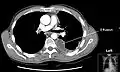

Chest computed tomography is more accurate for diagnosis and may be obtained to better characterize the presence, size, and characteristics of a pleural effusion. Lung ultrasound, nearly as accurate as CT and more accurate than chest X-ray, is increasingly being used at the point of care to diagnose pleural effusions, with the advantage that it is a safe, dynamic, and repeatable imaging modality.[15] To increase diagnostic accuracy of detection of pleural effusion sonographically, markers such as boomerang and VIP signs can be utilized.[16]

CT scan of the chest showing a left-sided pleural effusion. The fluid usually settles at the lowest space due to gravity; in this case, at the back because the patient is supine.- The lung expanding within an area of pleural effusion as seen by ultrasound